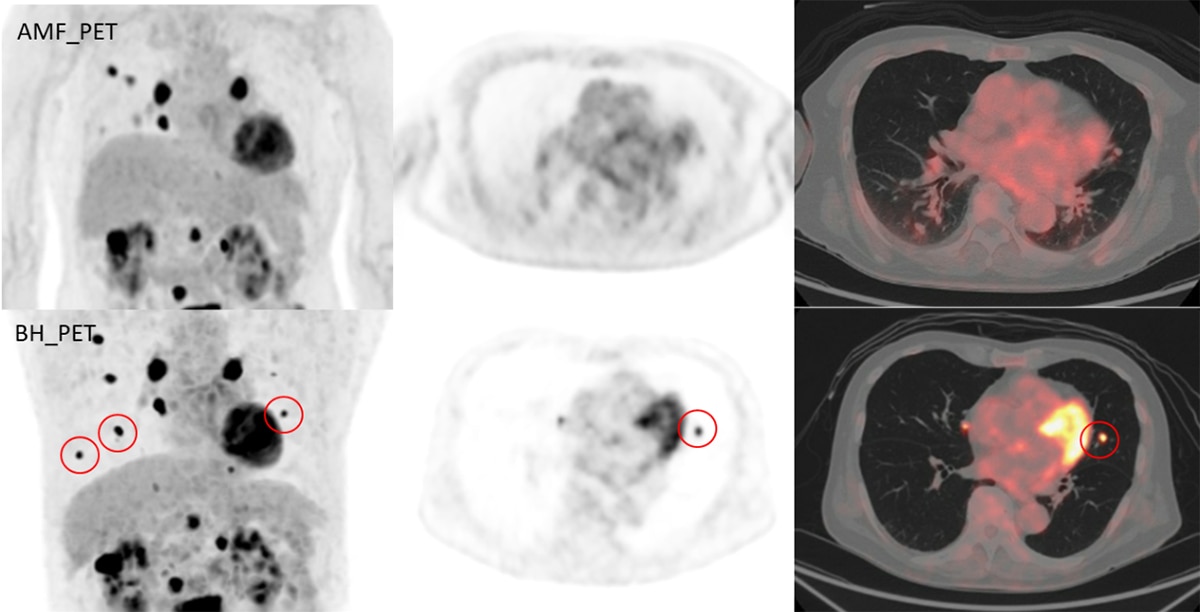

臨床に用いる収集条件は、核医学会が定める「18F-FDGを用いた全身PET撮像のためのファントム試験手順書」に準じたNEMA IEC Bodyファントムによる物理評価と、実際に診断するPET核医学専門医師の視覚評価(図4、図5)により決定しました。運用開始当初は、1bed 120秒撮像、Q.Clear β400で再構成を行っていましたが、収集時間をもう少し短く出来るのではないかと考え再検討し1bed 90秒撮像、Q.Clear β500の再構成としました。Precision DL(PDL)は、元の画像の特徴を大きく変えずにノイズが除去できるMediumを使用しています。

図4. 撮像時間90s

図5. 撮像時間120s